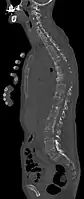

- Comparaison scanner/IRM pour des métastases ostéolytique d'un cancer du sein dans la colonne vertébrale

Scanner sagittal reconstruit, représentation dans la fenêtre osseuse. Comme la patiente avait des métastases dans toutes les régions du corps, elle ne pouvait pas lever les bras pour l'examen, ce pourquoi les mains sont présentées.

Scanner sagittale, parties molles. Outre les métastases dans la colonne vertébrale, qui envahissent en partie le canal médullaire vers l'arrière, métastases aussi dans le sternum. Plus des métastases dans le foie.

IRM natif avec pondération T1.

IRM sagittal natif avec pondération T1. On voit clairement l’extension jusqu'aux lames vertébrales.